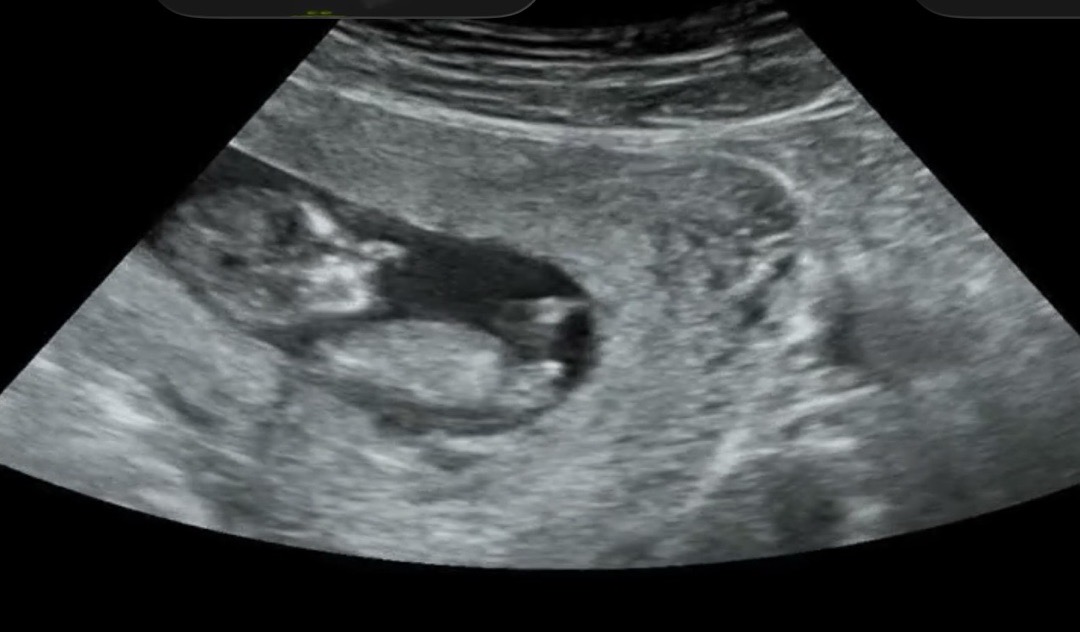

11주 6일 각도법! 한번만 봐주세용

어떻게 보이시나용 :) 둘째라 넘 궁금해요ㅎㅎ